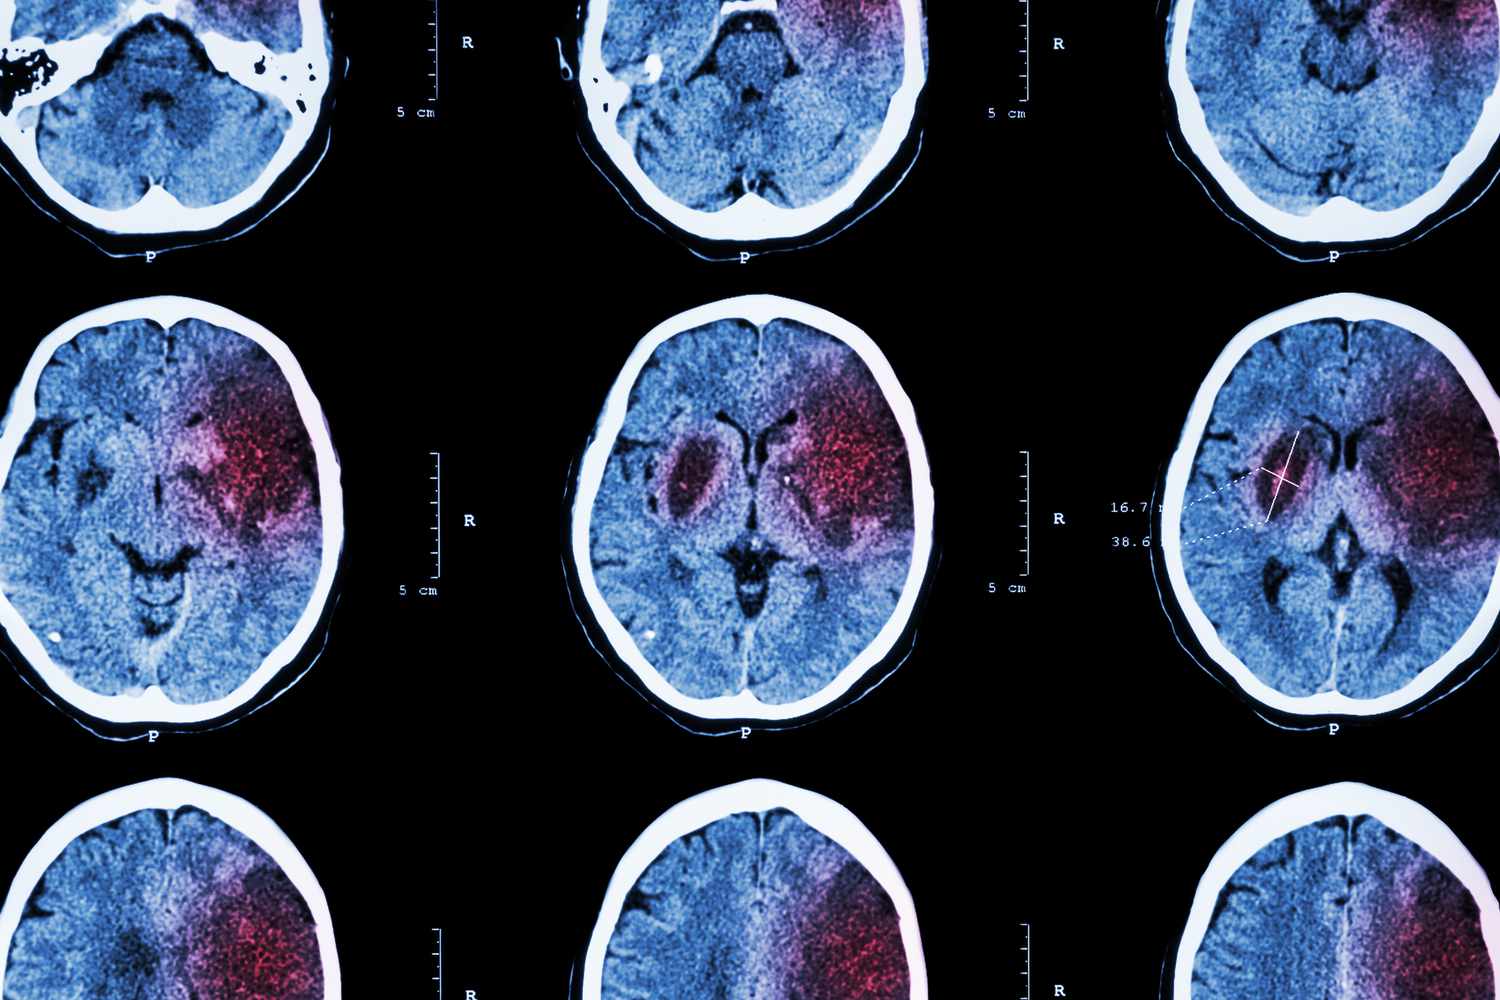

Stroke Warning Signs and Symptoms to Watch For

Strokes are a major health concern in the US, with warning signs called transient ischemic attacks or 'warning strokes' that mimic strokes but are temporary. Recognizing symptoms like balance issues, vision changes, facial drooping, arm weakness, speech difficulties, or a sudden headache using the 'BE FAST' mnemonic is crucial. Immediate medical attention is essential, as warning strokes often precede full strokes within days or weeks. Managing risk factors like high blood pressure and cholesterol can help prevent strokes.